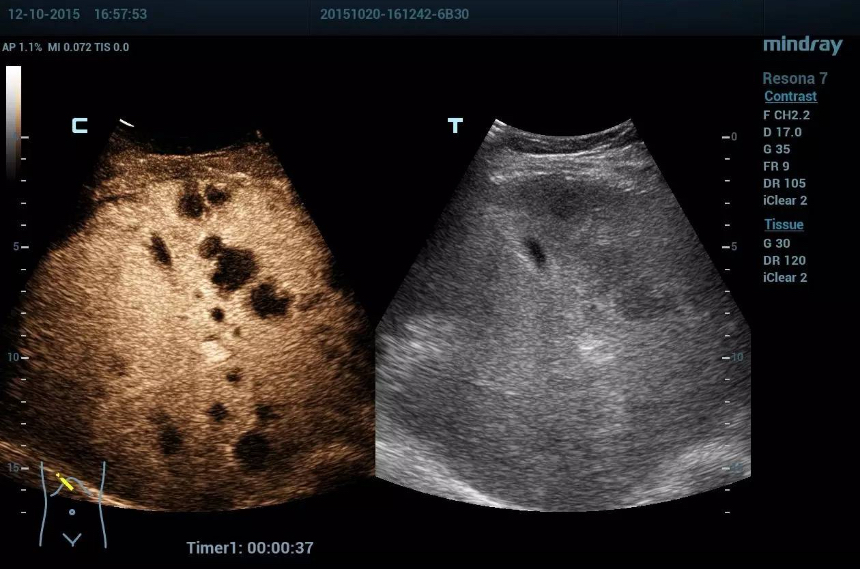

UWN+ Contrast Imaging: Greater Sensitive

Contrast-enhanced ultrasound (CEUS) has emerged as a valuable imaging modality for many applications. It generates significantly enhanced images, acquires greater sensitivity of minor signals and lengthens agent duration with lower MI (mechanical index).

Professor Christopher Dietrich from Germany recommends Resona 7 and its

UWN+ Contrast Imaging technique for being well integrated in his daily clinical practice. "With the support of contrast enhanced ultrasound technique, Resona 7 system allows reliable ultrasound imaging in terms of three most important quality parameters."